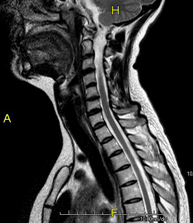

- RM de columna cervical

Prova diagnòstica no invasiva que consisteix en l'obtenció d'imatges d'alta definició anatòmica de la columna cervical mitjançant l'ús d'un camp electromagnètic i ones de ràdio (com un emissor i un receptor). No utilitza radiació ionitzant. Indicacions: traumatisme, degeneració de la columna, hèrnies. - RM de columna dorsal

Prova diagnòstica no invasiva que consisteix en l'obtenció d'imatges d'alta definició anatòmica de la columna cervical, mitjançant l'ús d'un camp electromagnètic i ones de ràdio (amb un emissor i un receptor). No utilitza radiació ionitzant. Indicacions: traumatisme, degeneració de la columna i hèrnies. - RM Columna Dorsal